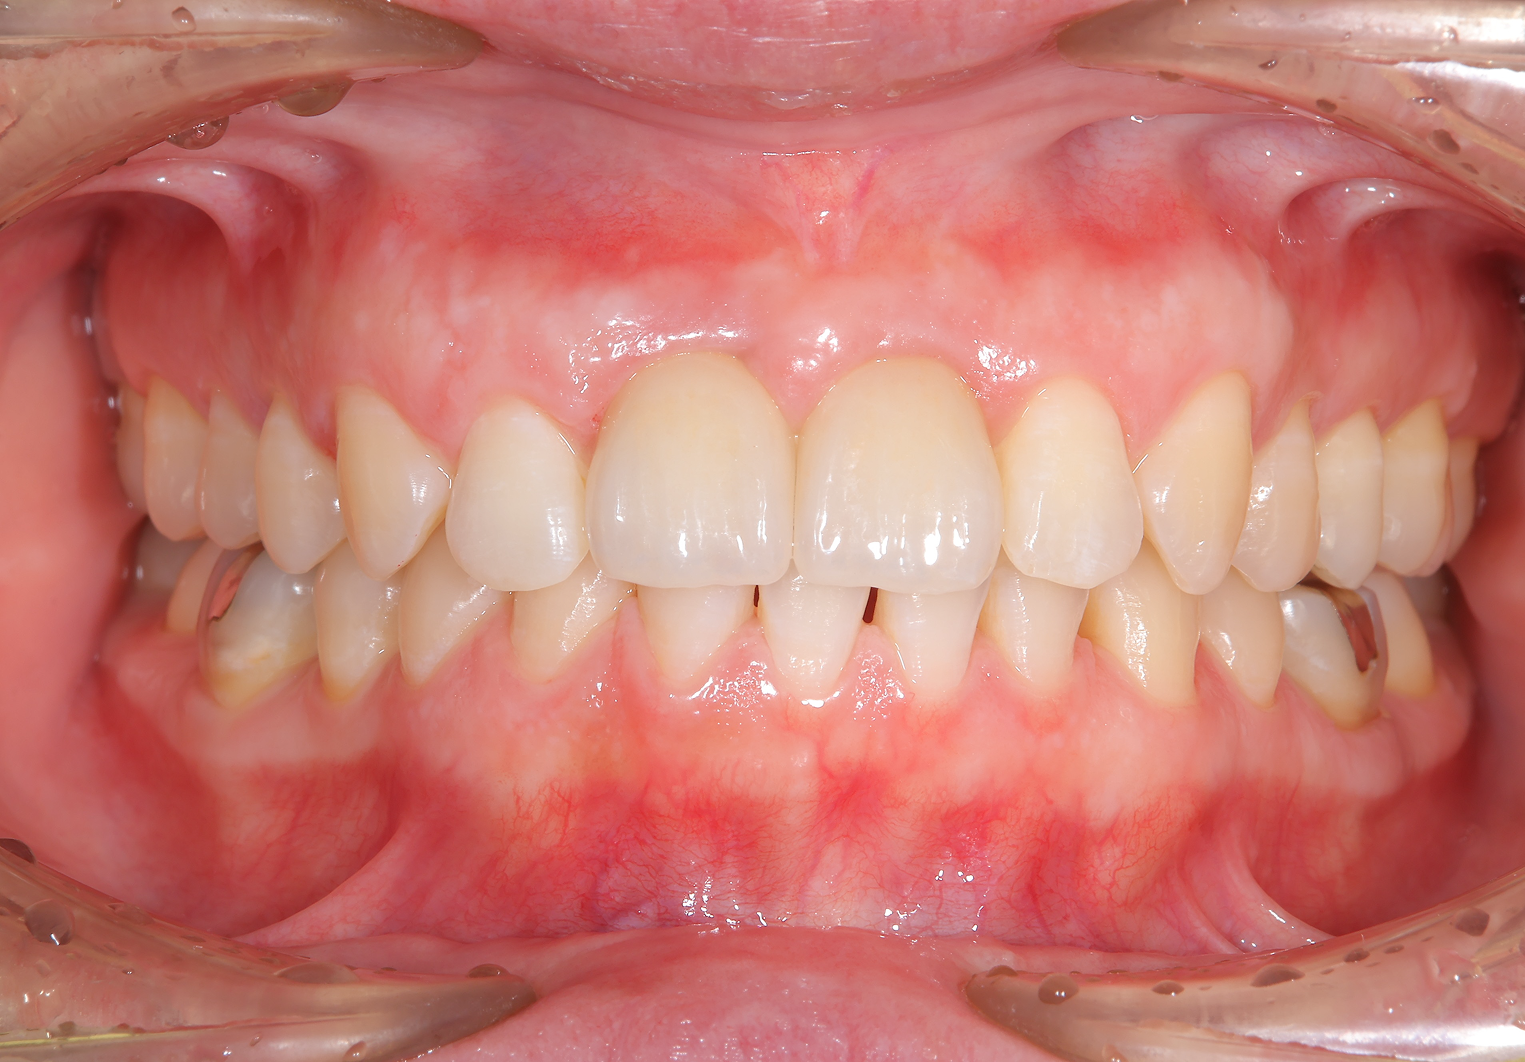

主訴:前歯の歯茎にできものができた。

治療概要:左上(写真では右)の真ん中の歯、根元の方にニキビのようなできものができています。診査の結果この歯は根が割れており、抜歯と判断しました。

治療前

治療後

前歯2本がインプラント治療に至った背景

お口全体を検査したところ、自覚はありませんでしたが、右の前歯もレントゲンを見ると歯の根の中腹あたりが溶けてしまっています。この歯も残念ながら抜歯となると判断しました。